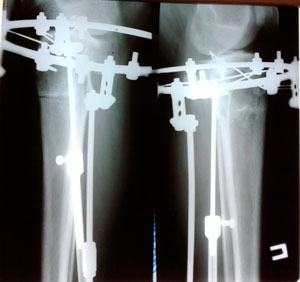

Дата операции - 19.04.2019г.

Дата снятия аппаратов - 26.07.2019г.

Срок сращения - 96 дней.